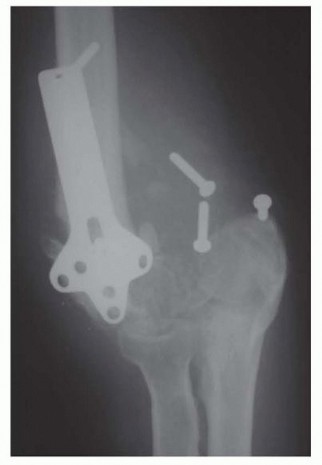

Operative Techniques in Hand, Wrist, and Elbow Sur